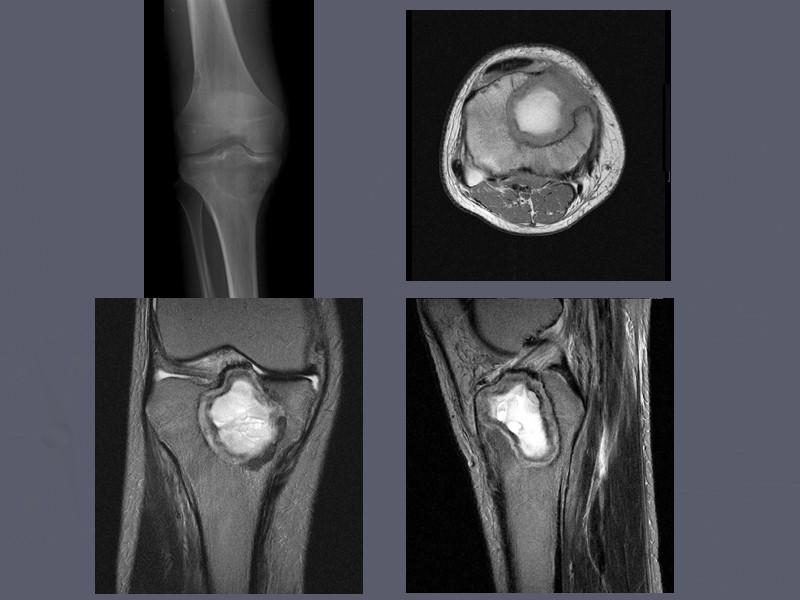

Остеосаркома коленного сустава: информация и поддержка

Раздел: Необычные решения